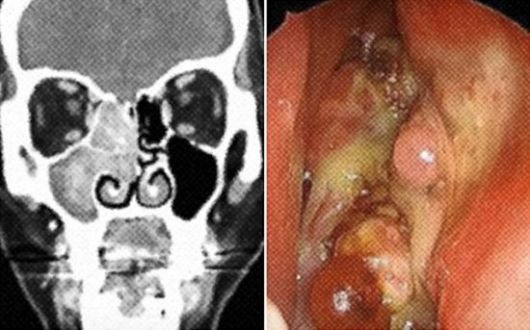

서울대병원에 따르면 부비동암은 코안의 빈 곳인 '비강' 주위의 동굴 같은 부비동에 발생하는 희소암이다. 비강과 부비동에 발생하는 악성종양은 인체의 악성종양 가운데 1% 이하이며, 두경부 악성종양의 3~5%를 차지한다. 보건복지부와 국립암센터가 발표한 2021년 국가암등록통계에 따르면 부비동암은 연간 인구 10만 명당 약 0.2~0.5명에 발생하며, 남성이 여성보다 2~3배 높은 발병률을 보인다.

부비동암은 종양이 주변 구조를 침범하는 양상에 따라 다른 증상을 보인다. 구강을 침범할 경우 의치나 치아가 흔들리거나 입을 열기 어려움(개구장애), 경구개의 종괴 현상 등이 나타날 수 있다. 안면을 침범할 경우 안면부 비대칭, 안면 통증, 이상 감각 등이 발생할 수 있다. 뇌 신경을 침범할 경우 여러 뇌 신경 마비를 일으킬 수도 있다. 눈 주변을 침범할 경우에는 부종과 결막부종, 외안근(안구를 움직이는 근육)의 운동 장애에 의한 복시, 안구 돌출, 시력 감소 등의 증상이 나타날 수 있다.

종양 사진. 서울아산병원 |

부비동암은 초기에 증상이 없거나 단순 코막힘, 콧물, 후각 감퇴 등 비염과 유사한 증상이 나타나 조기에 발견하기 어렵다. 암이 발생한 부위에만 머물러 있는 초기 단계에서 발견되면 치료 성과가 좋지만, 암을 발견했을 때는 이미 병이 상당히 진행됐을 가능성이 크다. 조기 발견도 어려운데 병의 진행이 빠른 것으로 나타났다. 주변에 뇌와 눈 같은 중요 신체 부위와 인접해 있지만, 아직 치료법이 확립되지 않은 상태다. 1960년대까지는 치료 성공률이 28% 수준이었으나 진단기법 발전과 적극적인 수술 및 치료로 1990년대에는 전반적인 생존율이 51%까지 높아졌다. 5년 생존율은 59.5%로 보고됐다.